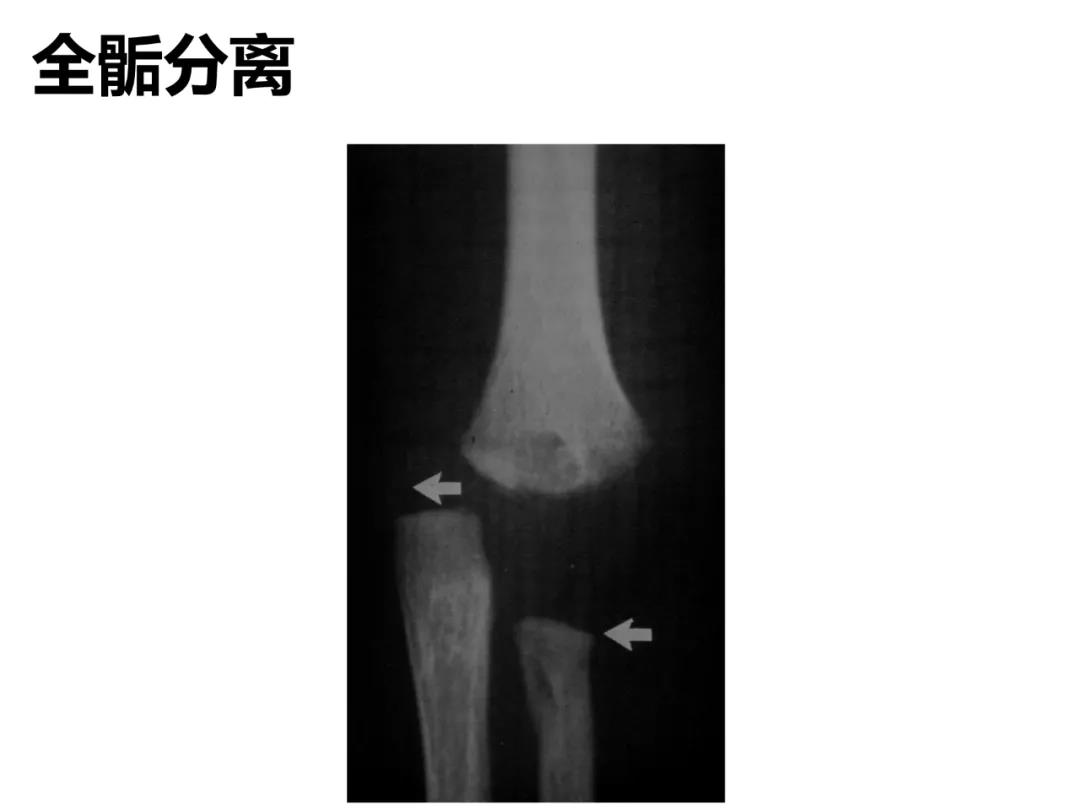

小儿骨科X线片汇总,临床读片宝典!